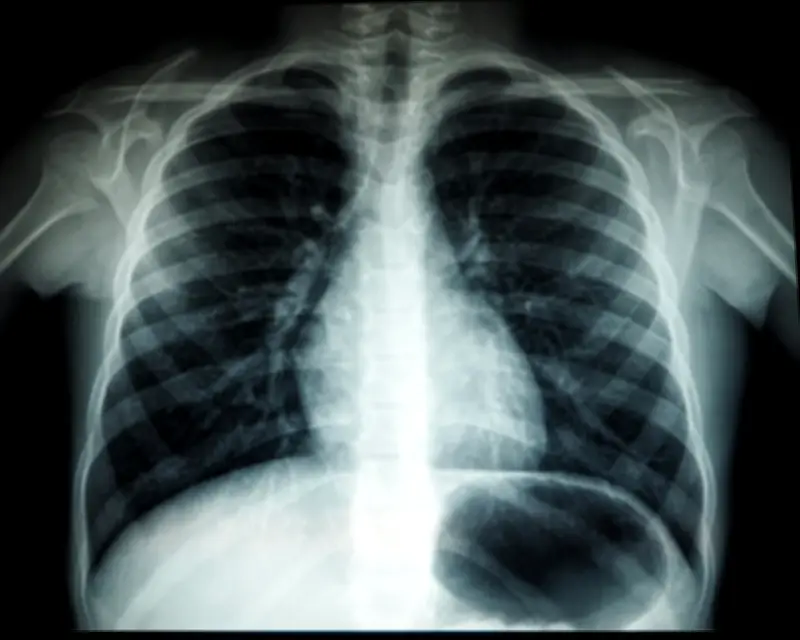

Tuberkulosis adalah penyakit berjangkit yang disebabkan oleh bakteria Mycobacterium tuberculosis. Penyakit ini merebak melalui udara dan boleh dijangkiti melalui hubungan rapat dengan individu yang telah dijangkiti.